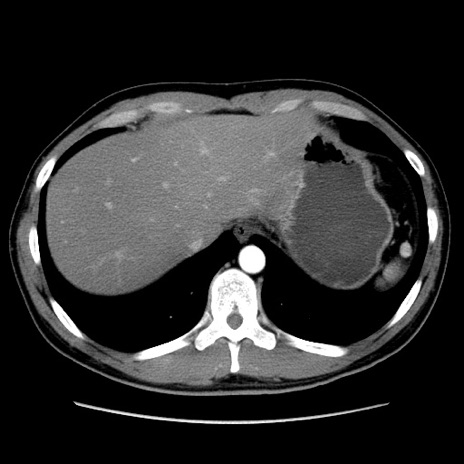

症例36(横断像)

【症例】20歳代 男性

【主訴】心窩部痛

【現病歴】今朝より上腹部痛あり。一旦軽快していたが再度出現したため救急要請。昨日夕に白身の魚を含む刺身を食べた。

【身体所見】BP 136/89mmHg、HR 74/min、BT 37.0℃、腹部:膨満、軟、心窩部に圧痛あり。反跳痛なし、筋性防御なし、腸雑音やや亢進あり。

【データ】WBC 17700、CRP 0.48